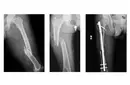

28 yıl önce trafik kazası sonucu sol kalça sağa doğru eğilerek asimetri oluşmuş sol simfizis pubis sağ simfisiz pubise dayanmış hatta sağ kalçada sağa doğru kaymış simfizis pubis penil köke baskı yapmakta, ben bu ameliyatı yapacak dr bulamadım, bana ameliyat yağabilecek dr önerebilir misiniz. Tetkik be görüntüleri göndereceğim bi mail adresi yada Watsapp numarası verirseniz hemen gönderirim. Laf olsun diye sormuyorum gerçekten pelvis eğriliğini düzeltecek dr yok sanki bu ülkede yıllardır bulamadım. Lütfen yardımcı olurmusunuz, Türkiye’deki tek vaka olabilir mişim öyle diyen dr lar da var. Yardımlarınız için şimdiden teşekkür ederim